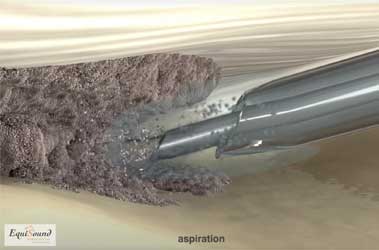

Tenex est une technique de traitement développée il y a 5 ans aux États-Unis pour traiter des pathologies tendineuses chroniques chez l’être humain (atteinte chronique des tendons d’Achille, épine calcanéenne, dégénérescence du tendon rotulien, etc.). Cette technique utilise des ultrasons (comme pour un détartrage) afin de détruire le tissu endommagé et de stimuler ainsi le processus de cicatrisation pour offrir une nouvelle chance de guérison. La fréquence ultrasonore est spécifiquement choisie pour ne détruire que les tissus durs (fibrose et minéralisations) et ne pas causer de dommages au tissu tendineux sain. Le traitement par ultrasons est appliqué à l’aide d’une aiguille creuse dans un tube creux (cf. photo 8a). Durant le traitement, un flux de NaCl sort de l’aiguille creuse et est simultanément aspiré via le tube creux (cf. photos 8b et 8c). Cette solution aqueuse permet avant tout l’évacuation du tissu débridé mais aussi le refroidissement de l’aiguille qui chauffe fortement en raison des ultrasons.

L’aiguille étant introduite de manière échoguidée via des incisions de ponction dans la peau, ce traitement est mini-invasif. De ce fait, le patient récupère plus rapidement et nécessite peu de soins de plaie. Ceci permet aussi le positionnement exact de l’aiguille dans la zone dégénérative de la structure pathologique.

Tenex est une nouvelle technique de traitement chirurgical mini-invasif, destinée aux chevaux et aux chiens souffrant de tendinopathies dégénératives chroniques. Grâce à des ultrasons et à une aspiration, le tissu cicatriciel chronique est débridé pour donner de nouvelles chances de guérison